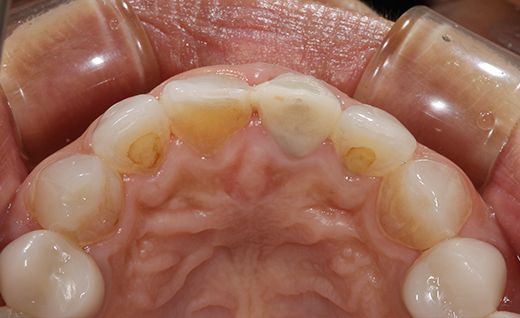

施術前

「昔保険で入れた前歯の色が、年々まわりの歯と合わなくなってきて…笑ったときにどうしても気になってしまうんです」 とご相談いただきました。 変色や色味の違いが気になるということで、今回は保険の被せ物を取り外し、自然な見た目と透明感が特徴のオールセラミックに交換する治療をご提案しました。